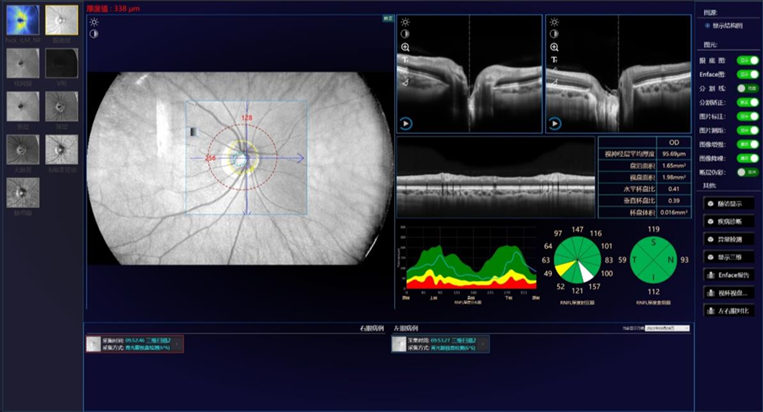

Escaneo de Glaucoma

Mácula + Disco óptico 6mm x 6mm y 12mm x 6mm

Reporte de Análisis de Disco Óptico Glaucomatoso

• Análisis de capa de fibra nervios retinal

• Análisis de relación de Copa a Disco

• Área del margen del Disco

• Área del disco óptico

• Relación Copa Disco

• Análisis de consistencia interocular

• Análisis de seguimiento

• Etc.